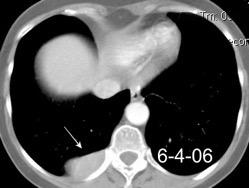

Hemorrágica………….30-70 UH

Extravasación iv. con sangrado activo……….>90 UH

“Simpático”………….,,,,<15 UH

Durso AM et al. Penetrating Thoracic Injury. Radiol Clin N Am 2015.

Urogénico……………….< 15 UH

Entérico.. ………………+/- 15UH

Biliar, Quiloso……………..<0 UH

Urinoma

Hemotórax

Quilotórax

Absceso pared en empiema Tb

Derrame no complicado + hematoma mediastínico

68 UH

Empiema pleural post-trauma

12UH

Abramowitz1 Y et al. Pleural Effusion: Characterization with CT Attenuation Values and CT Appearance .AJR 2008